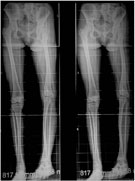

The full length x-ray showing the difference in lengths between the two limbs. The shortening was measured clinically using blocks and palpation of both ASIS (anterior superior iliac spines) and then tallied with the difference on the full length x-ray. |